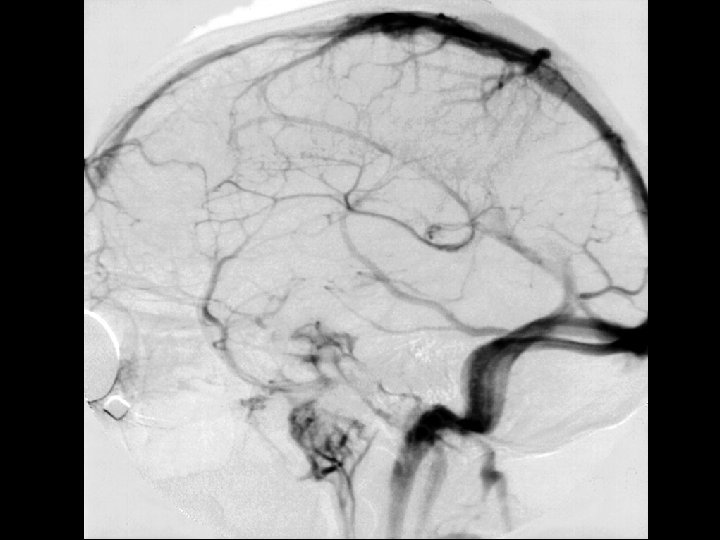

Angiographic digression to aid the understanding of venous angiography Michigan Neurosurgery

Arterial phase Michigan Neurosurgery